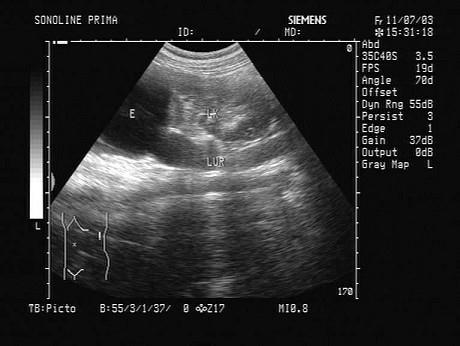

根据超声图像,该病例最可能的诊断?(?)A.肾上极囊肿B.肾脏积水C.肾脏肿瘤D.重复肾E.肾脓肿

问题 根据超声图像,该病例最可能的诊断?(?)

选项 A.肾上极囊肿 B.肾脏积水 C.肾脏肿瘤 D.重复肾 E.肾脓肿

答案 D